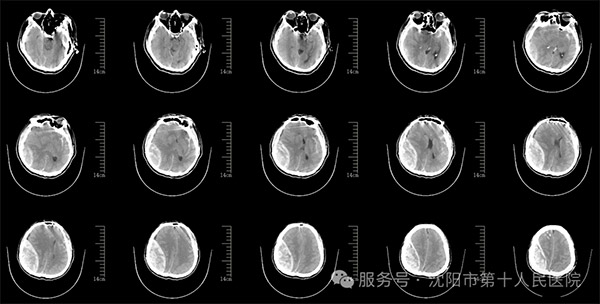

该患者在突发头晕头部摔伤,摔伤后立即被送往医院进行紧急救治。由于头部受到重创,到院时已完全昏迷,四肢瘫痪,瞳孔散大,生命垂危,急诊室予以积极的抢救,头CT检查发现患者颅内出血严重并中线移位脑疝。时间就是生命,神经中心外科景雪峰主任带领团队迅速实施开颅手术,清除了颅内的血肿,并去除了部分颅骨以降低颅内压,从而挽救了患者的生命。手术后,患者仍昏迷病情极为危重,但经过神经外科及神经重症等多学科多位专家协同会诊治疗下,患者逐步恢复自主呼吸脱离呼吸机,由重症医学科转至神经中心病房。

外伤术前影像资料